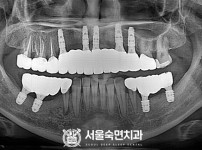

임플란트-전후사진2